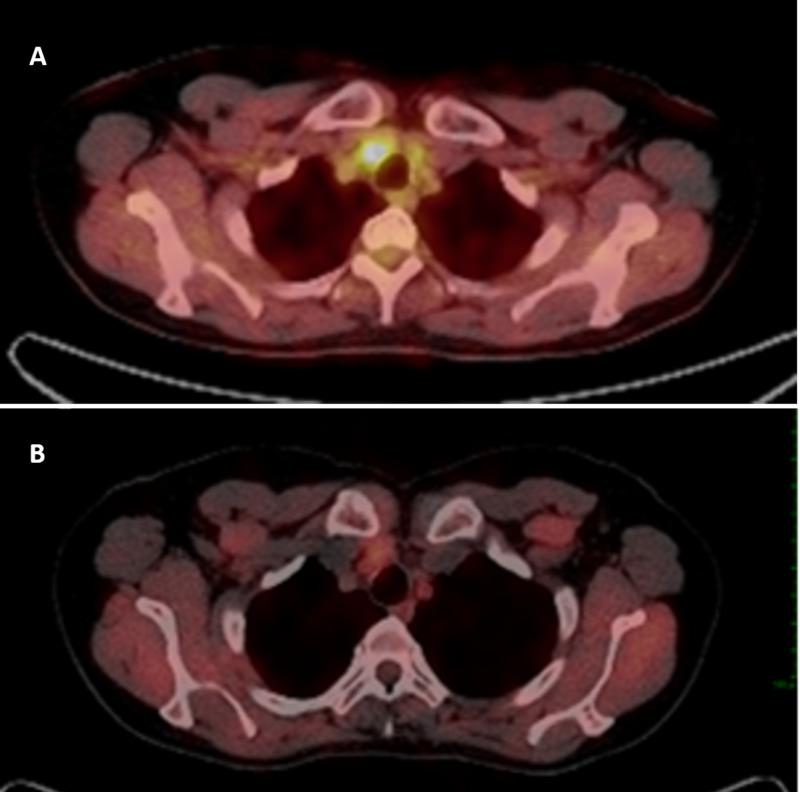

Currently, the standard treatment for women with metastatic cervical cancer is palliative chemotherapy with or without bevacizumab. Patients with oligometastatic disease seem to have a better prognosis than those with disseminated disease. We present two cases of women with mediastinal oligometastatic disease from cervical cancer treated with mediastinal radiotherapy concurrent with intravenous cisplatin. Both patients achieved a complete response that remained after a follow-up of more than three years.

目前,转移性宫颈癌女性的标准治疗方法是姑息性化疗,可联合或不联合贝伐单抗。寡转移疾病患者的预后似乎比播散性疾病患者更好。我们报告了两例宫颈癌纵隔寡转移疾病的女性患者,她们接受了纵隔放疗并同时静脉注射顺铂治疗。两名患者均获得了完全缓解,且在三年多的随访后仍保持缓解状态。